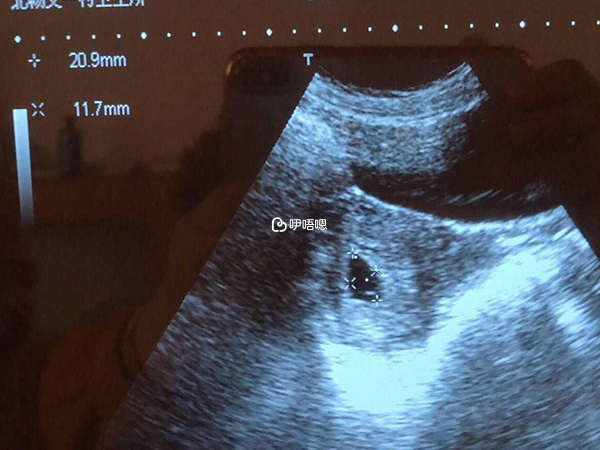

7、已生男孩b超孕囊圖片一覽

通過陰式b超得出的孕囊資料,不管是長度也好還是寬度也好都是很真實的,結果會有3個數據,長、寬、高,如果b超看到的孕囊最長徑在13-18毫米之間,三個資料中其中一個數據與其他兩個資料相差較大,比如14×15×7mm,屬於長條形,可能生男寶。

B超是孕初期重要檢查專案,在懷孕12周以前,寶寶還沒有發育成形,只能看到一個小小的孕囊,有人認為男孩女孩性別不同,孕囊形狀也不一樣,很多已生寶媽驗證,懷男孩的孕囊大多數表現為茄子型的狀態,在懷孕兩個月左右,胚胎自身會長至約2.5釐米,體重約4克左右,此時的孕囊如果呈長條形或茄子形狀生男孩的機率較大。